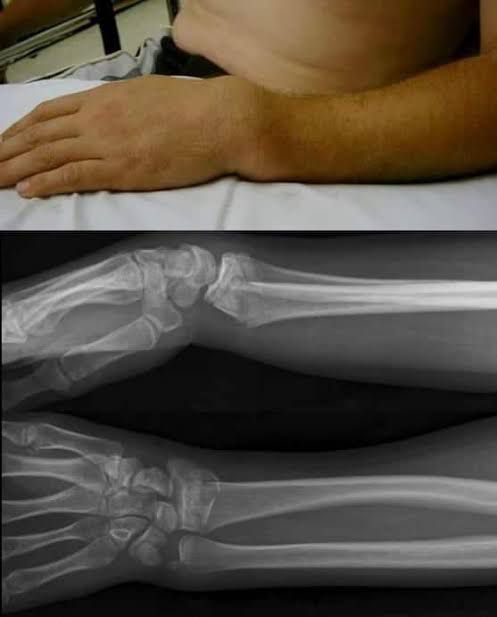

A Colles fracture is a type of broken wrist (fracture). It's also called a distal (away from the center of the body) fracture with dorsal angulation (an upward angle). A Colles fracture is a very painful and serious injury. Go to your nearest emergency department if you suspect you have any type of wrist fracture.